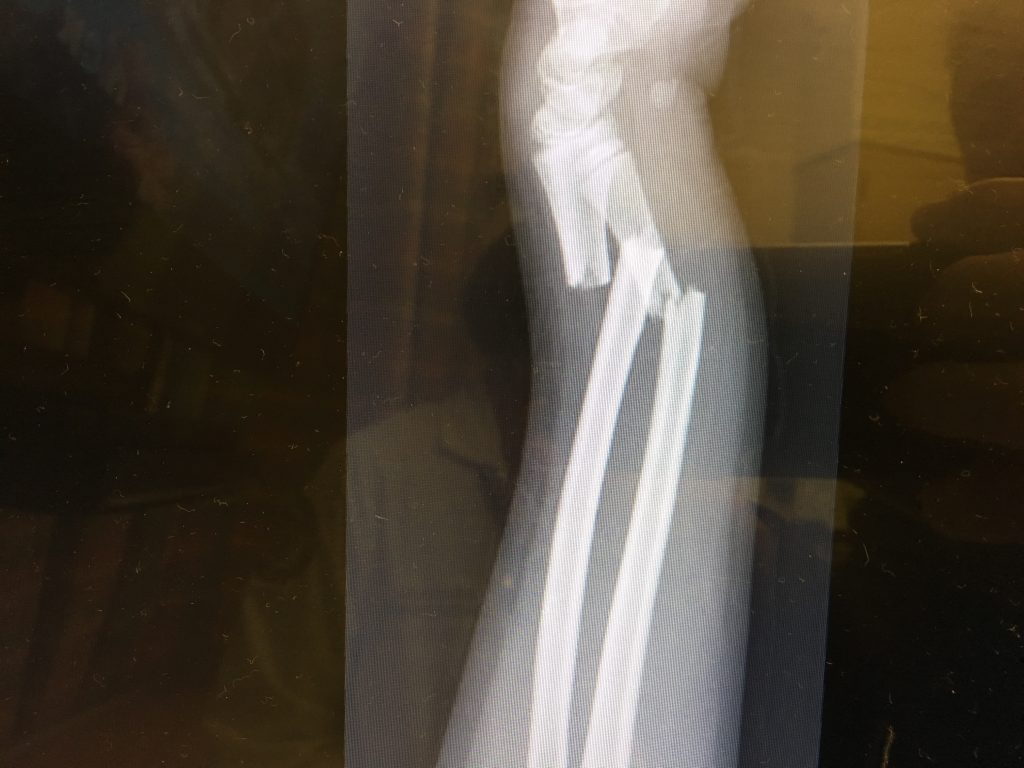

While they were treating me, they discovered that one of the bones had broken through the skin a little bit which made everything more complicated. I had surgery to clean and repair the bones. I had two metal plates put on the bones and spent 3 nights in the hospital.